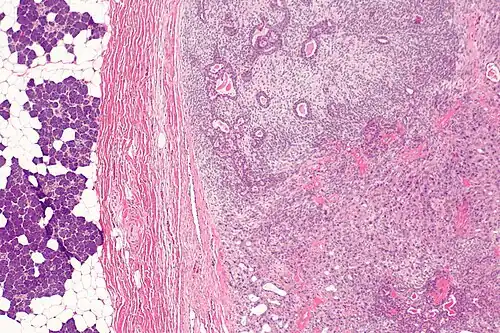

Clinicamente se caracteriza como uma massa de longa data que passou por recente crescimento rápido, mas pode ocasionar dor, parestesia ou paralisia facial, assim como ulceração da pele e disfagia em casos avançados.[43][47] Na ressonância magnética, o componente benigno (encapsulado) tende a ter uma intensidade de sinal variável devido à natureza arquitetural do adenoma pleomórfico, enquanto o componente invasivo maligno apresenta baixa a média intensidade de sinal em T2 devido a hemorragia e necrose.[43][48] Histologicamente, apresenta-se como um adenoma pleomórfico (componente benigno) associado a um componente carcinomatoso que pode ser um carcinoma do ducto salivar, carcinoma mioepitelial (usualmente de baixo grau), adenocarcinoma (usualmente de alto grau) ou carcinoma epitelial-mioepitelial.[43]